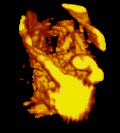

A 3D Power Doppler image of vasculature in 20-week placenta -